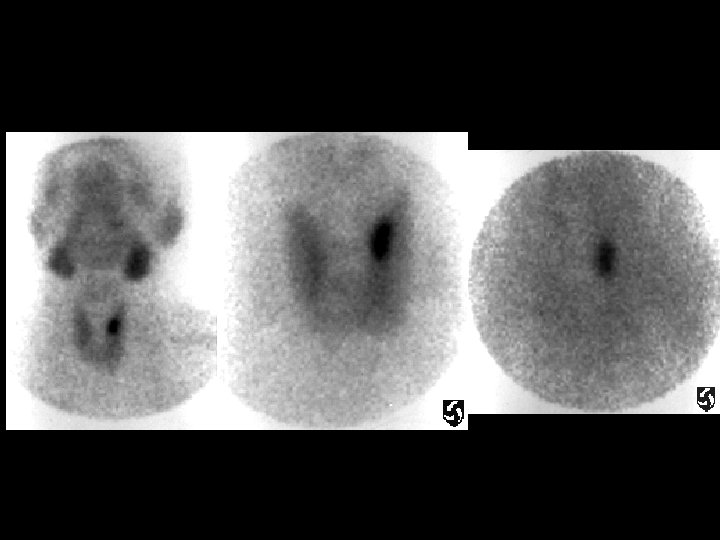

Bilateral pars fractures • Findings: – Planar images of the spine demonstrate subtle increased activity at L 5 – Coronal and axial SPECT images are diagnostic • ddx: – NONE! – This is an Aunt Minnie!